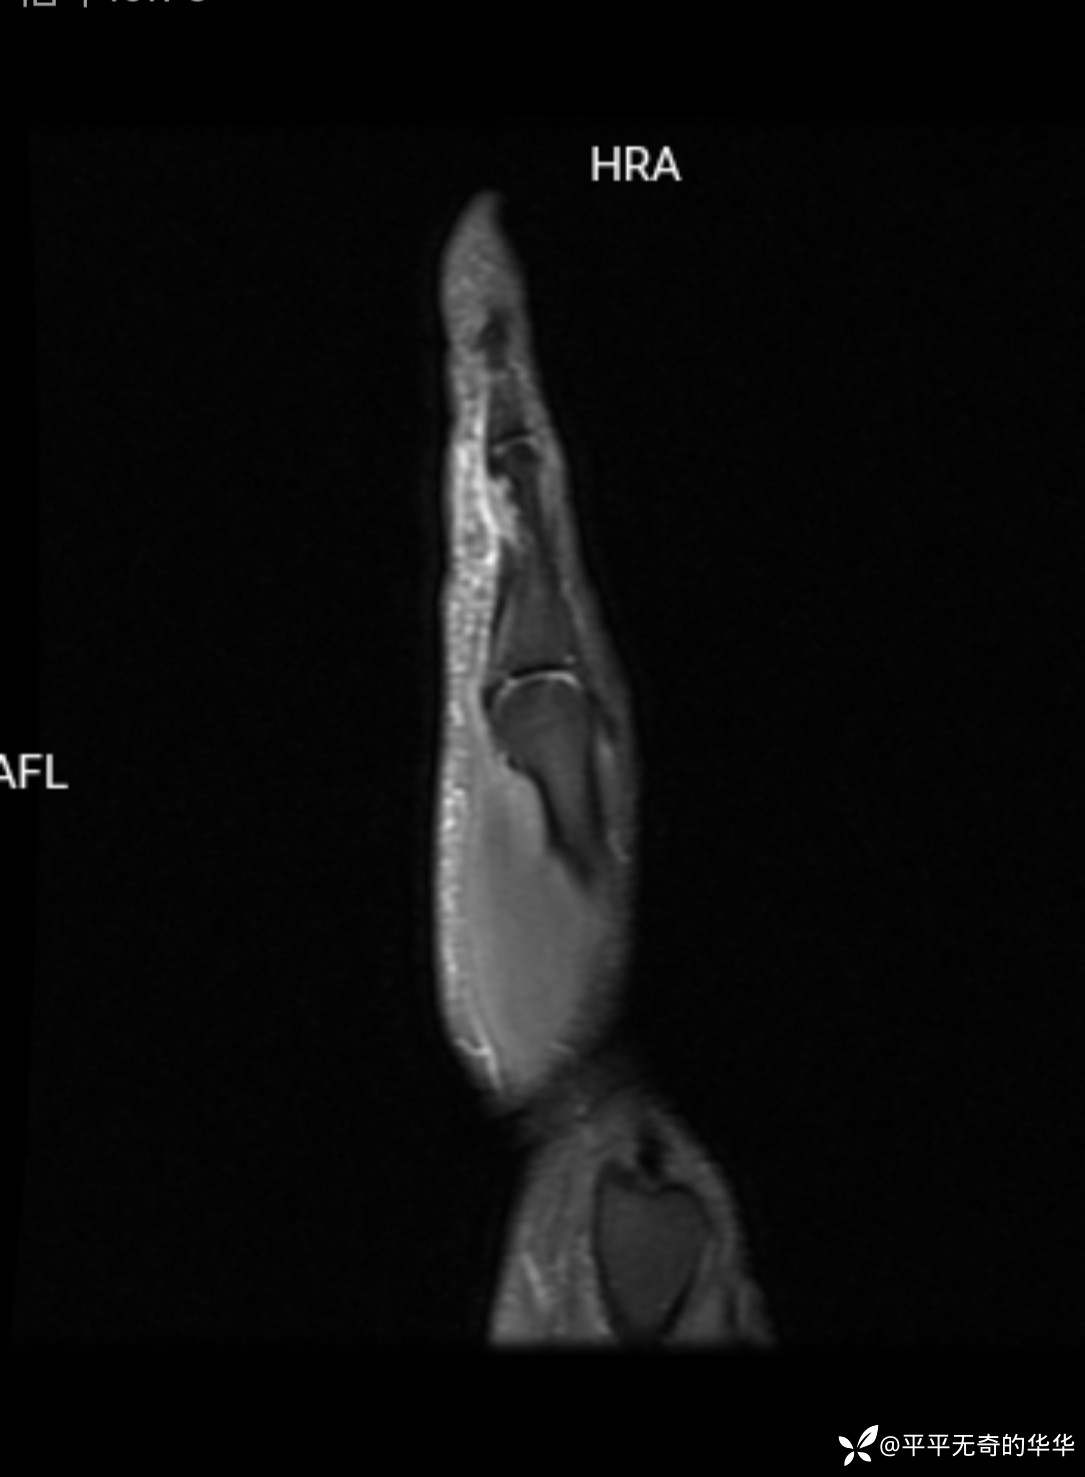

其他手指屈肌腱影像连续性良好